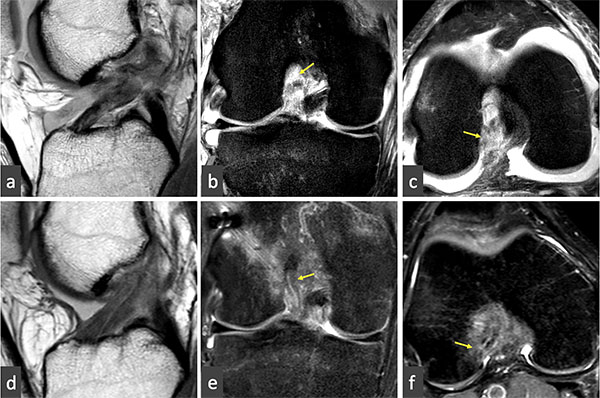

Sherman7 en el año 1991 presentó una clasificación que luego fue modificada por Van Der List y DiFelice en 20168 para lesiones completas del LCA donde contempla el nivel de la lesión (fig. 10). Considerando al LCA en su extensión completa como el 100%, las lesiones tipo I corresponden a las avulsiones localizadas dentro del 10% proximal (femoral). La prevalencia de estas lesiones en resonancia magnética es de aproximadamente 16% y es más frecuente en pacientes mayores de 35 años.18 Las lesiones que comprometen únicamente una banda se consideran Ia. Las tipo II corresponden al tercio proximal, entre 75 y 90% de las fibras proximales; las tipo III al tercio medio, entre 25 y 75% de las fibras del ligamento; las tipo IV son lesiones distales; las tipo V son lesiones con avulsión ósea distal. La reparación está indicada idealmente en las lesiones tipo I. A partir de las lesiones tipo II los autores sugieren reconstrucción del ligamento, y, en caso de ser posible, asociar un retensado de las fibras remanentes que conserven más del 90% de la extensión.

Figura 10: Clasificación propuesta por Sherman modificada por DiFelice. Lesiones tipo I (a), avulsiones dentro del 10% proximal; las lesiones que comprometen únicamente una banda se consideran Ia (b); las tipo II (c) entre 75 y 90% de las fibras proximales; las tipo III (d) entre 25 y 75% de las fibras del ligamento; las tipo IV (e) son lesiones distales; las tipo V (f) lesiones con avulsión ósea distal.

En nuestra experiencia inicial, los pacientes fueron operados antes del mes de la lesión. Realizaron una evaluación previa con kinesioterapia hasta lograr movilidad completa previo a la reparación. Clínicamente presentaban maniobras de inestabilidad positivas y resonancia magnética en la que se evidenció una lesión dentro del 10% proximal (fig. 11a). Como se describió previamente, la técnica que se utilizó fue fijación de las fibras del LCA con un botón cortical adicionando un tutor interno. Evolucionaron inicialmente con una rápida recuperación del rango de movilidad y del tono muscular del cuádriceps dentro del primer mes postoperatorio. La RM control a los 3 meses evidenció un LCA en proceso de cicatrización (fig. 11b).

Figura 11: Corte sagital (a), coronal (b) y axial (c) de resonancia magnética donde se observa lesión proximal del LCA. La lesión se ubica dentro del 10% proximal de las fibras del ligamento. Observese la continuidad lineal, la regularización de los bordes y homogeneidad de las fibras del LCA 3 meses posterior a la reparación en el corte sagital (d), coronal (e) y axial (f).